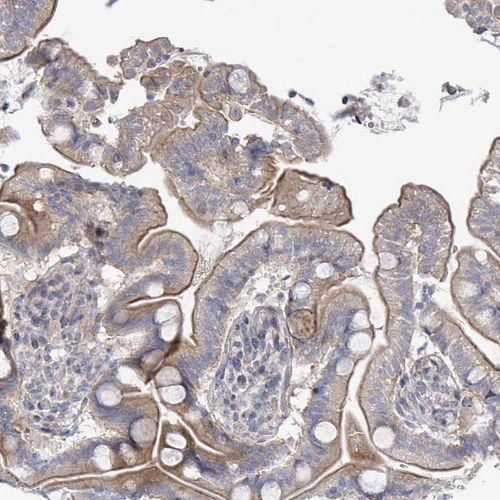

Immunohistochemical staining of human lymph node shows moderate to strong positivity in lymphoid cells.